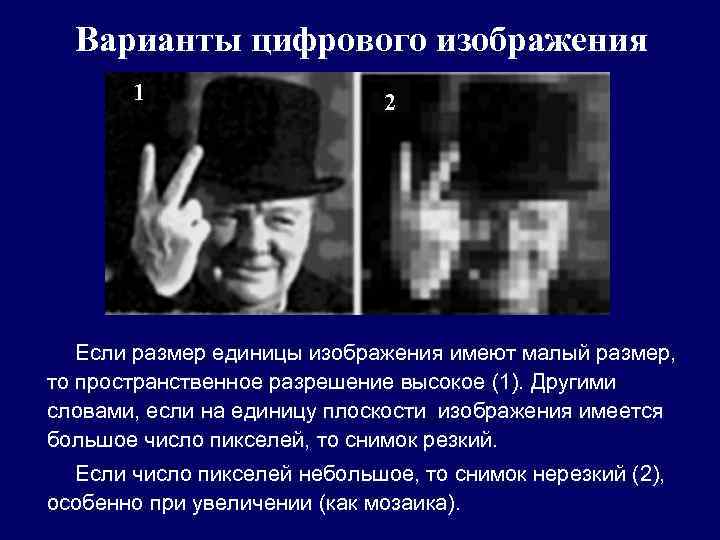

Варианты цифрового изображения 1 2 Если размер единицы изображения имеют малый размер, то пространственное разрешение высокое (1). Другими словами, если на единицу плоскости изображения имеется большое число пикселей, то снимок резкий. Если число пикселей небольшое, то снимок нерезкий (2), особенно при увеличении (как мозаика).